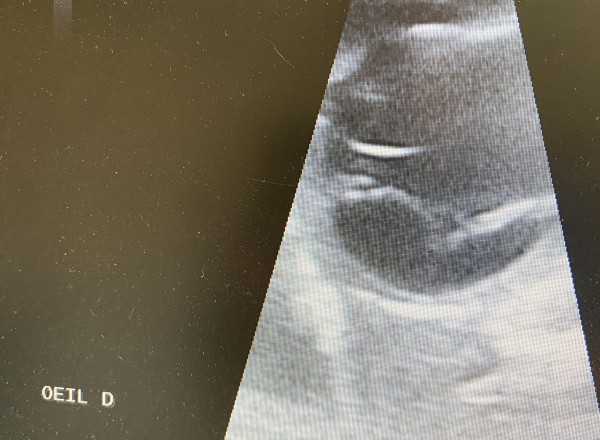

• Échographie oculaire (si l’œil est opaque ou non visuel)

Ophtalmoscopie directe et indirecte. Examen lampe a fente. Examen du fond d’œil. Tonométrie. Échographie oculaire